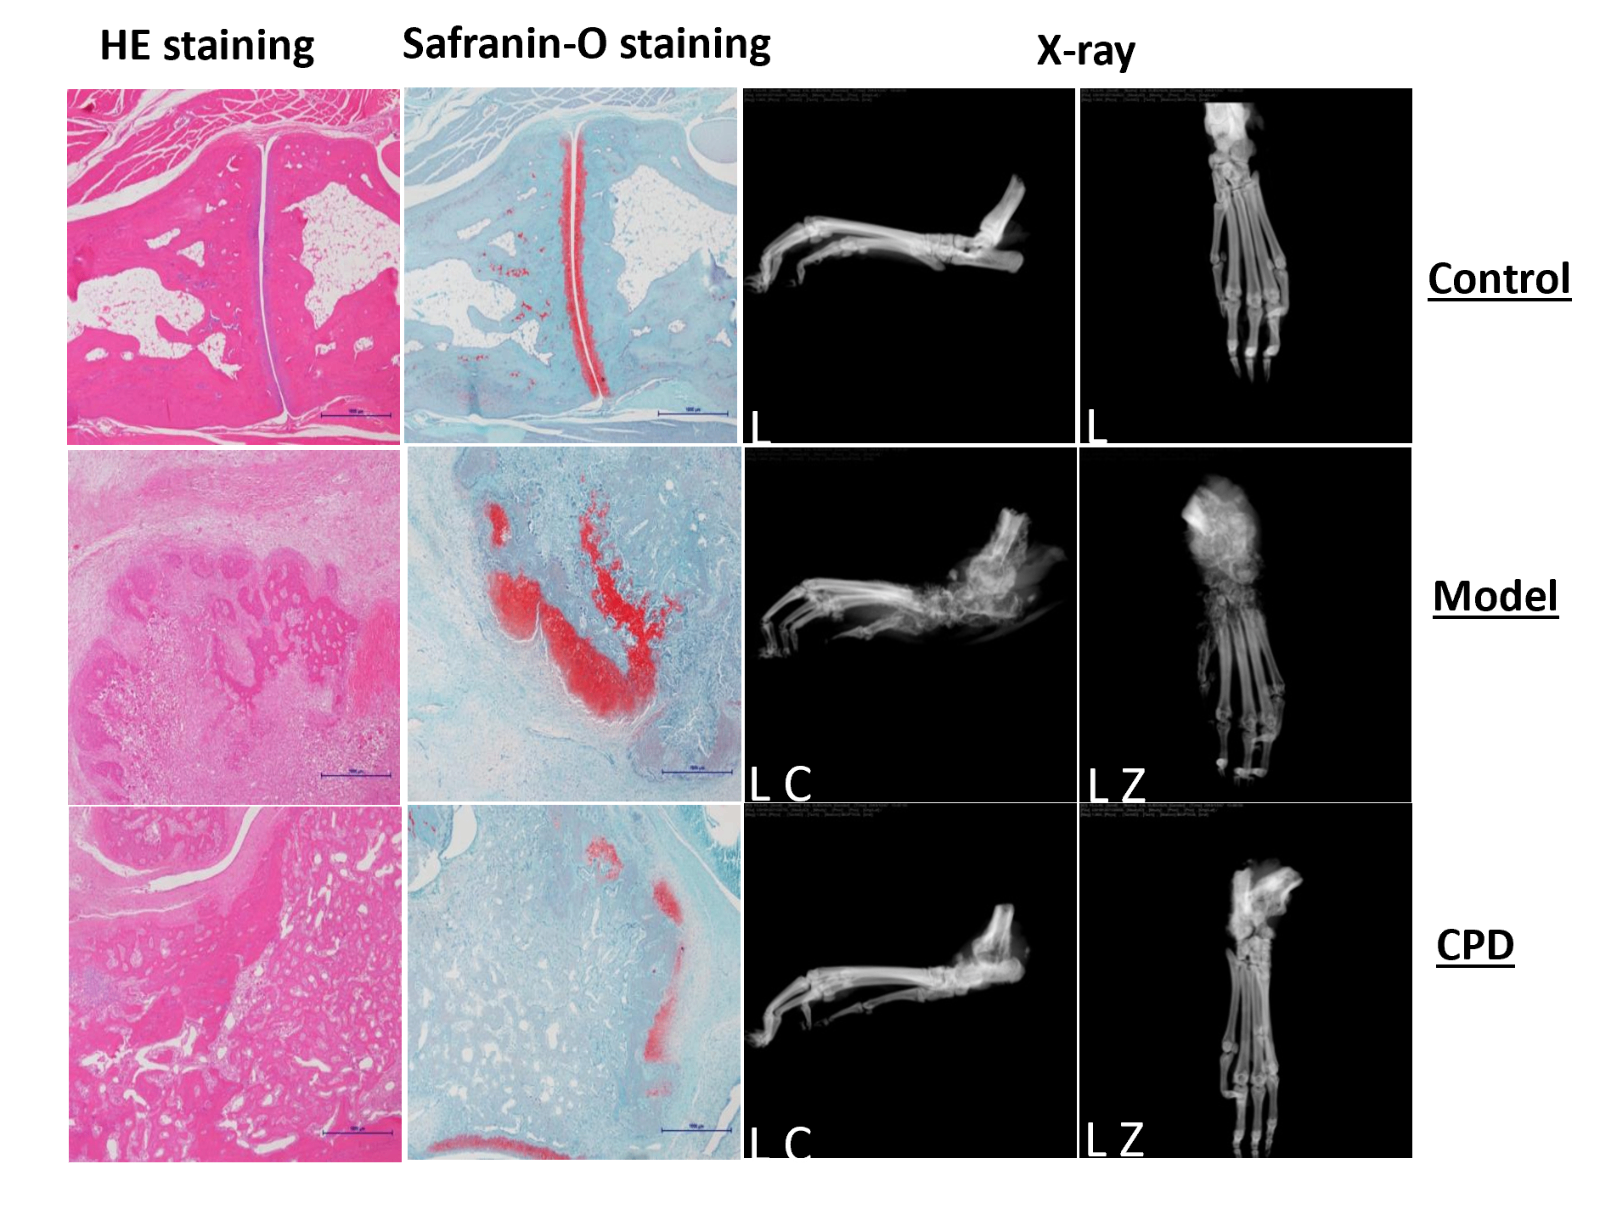

Model evaluation

Model anatomy and histopathological analysis confirm model adequacy for preclinical RA compound testing.

Also, both clinical score and joint swelling show model relevancy for RA and responsiveness to tofacitinib, a Janus kinase (JAK) inhibitor.